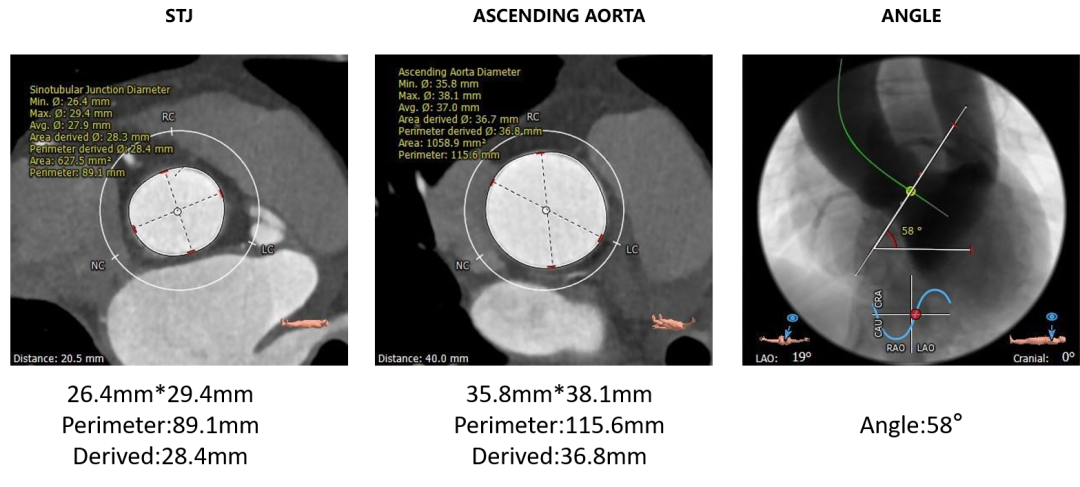

• 瓣环水平夹角为58°,右侧髂总动脉条状钙化,入路血管管径良好。

主动脉根部测量